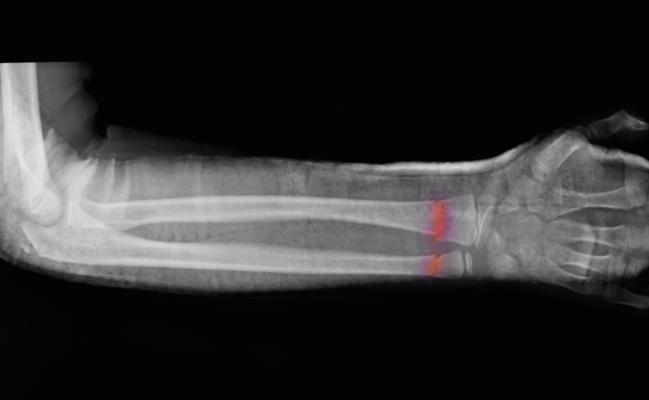

March 30, 2022 — Artificial intelligence (AI) is an effective tool for fracture detection that has potential to aid clinicians in busy emergency departments, according to a study in Radiology.

Missed or delayed diagnosis of fractures on X-ray is a common error with potentially serious implications for the patient. Lack of timely access to expert opinion as the growth in imaging volumes continues to outpace radiologist recruitment only makes the problem worse.

The researchers found no statistically significant differences between clinician and AI performance. AI’s sensitivity for detecting fractures was 91-92%.